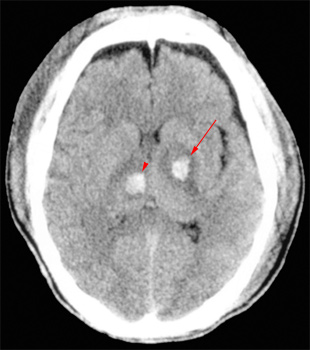

Head CT > Trauma > Diffuse Axonal Injury

Diffuse Axonal Injury

Diffuse

axonal injury is often referred to as "shear injury". It is

the most common cause of significant morbidity in CNS trauma. Fifty percent

of all primary intra-axial injuries are diffuse axonal injuries. Acceleration,

deceleration and rotational forces cause portions of the brain with different

densities to move relative to each other resulting in the deformation

and tearing of axons. Immediate loss of consciousness is typical of these

injuries. The CT of a patient with diffuse axonal injury may be normal

despite the patient's presentation with a profound neurological deficit.

With CT, diffuse axonal injury may appear as ill-defined areas of high

density or hemorrhage in characteristic locations. The injury occurs in

a sequential pattern of locations based on the severity of the trauma.

The following list of diffuse axonal injury locations is ordered with

the most likely location listed first followed by successively less likely

locations:

- Subcortical white matter

- Posterior limb internal capsule

- Corpus callosum

- Dorsolateral midbrain